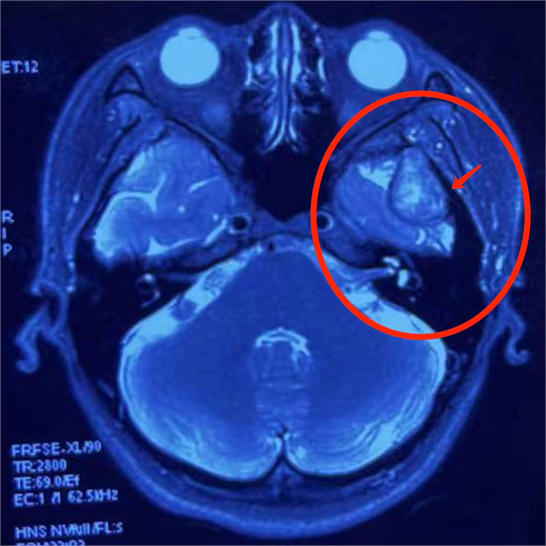

最可怕的是,脸上凸起的肿物只有3CM左右,但是,肿瘤一直往深处发展已经侵蚀到颅底,大概有6*4cm的大小!

MRI提示:肿瘤已经侵入颅内

"花姐的这个肿瘤是发生在腮腺深叶并向颅内发展的罕见巨大肿瘤,但其实腮腺肿瘤并不罕见,但是瘤体巨大,增长较快且侵蚀入颅内的实属罕见。并且这种肿瘤难以发现,早期没有明显的症状与不适,部分患者会出现面部不对称、面瘫(口角歪斜、闭眼不全等)等症状,容易复发甚至恶变,需要尽快手术去除。"张国权主任表示。